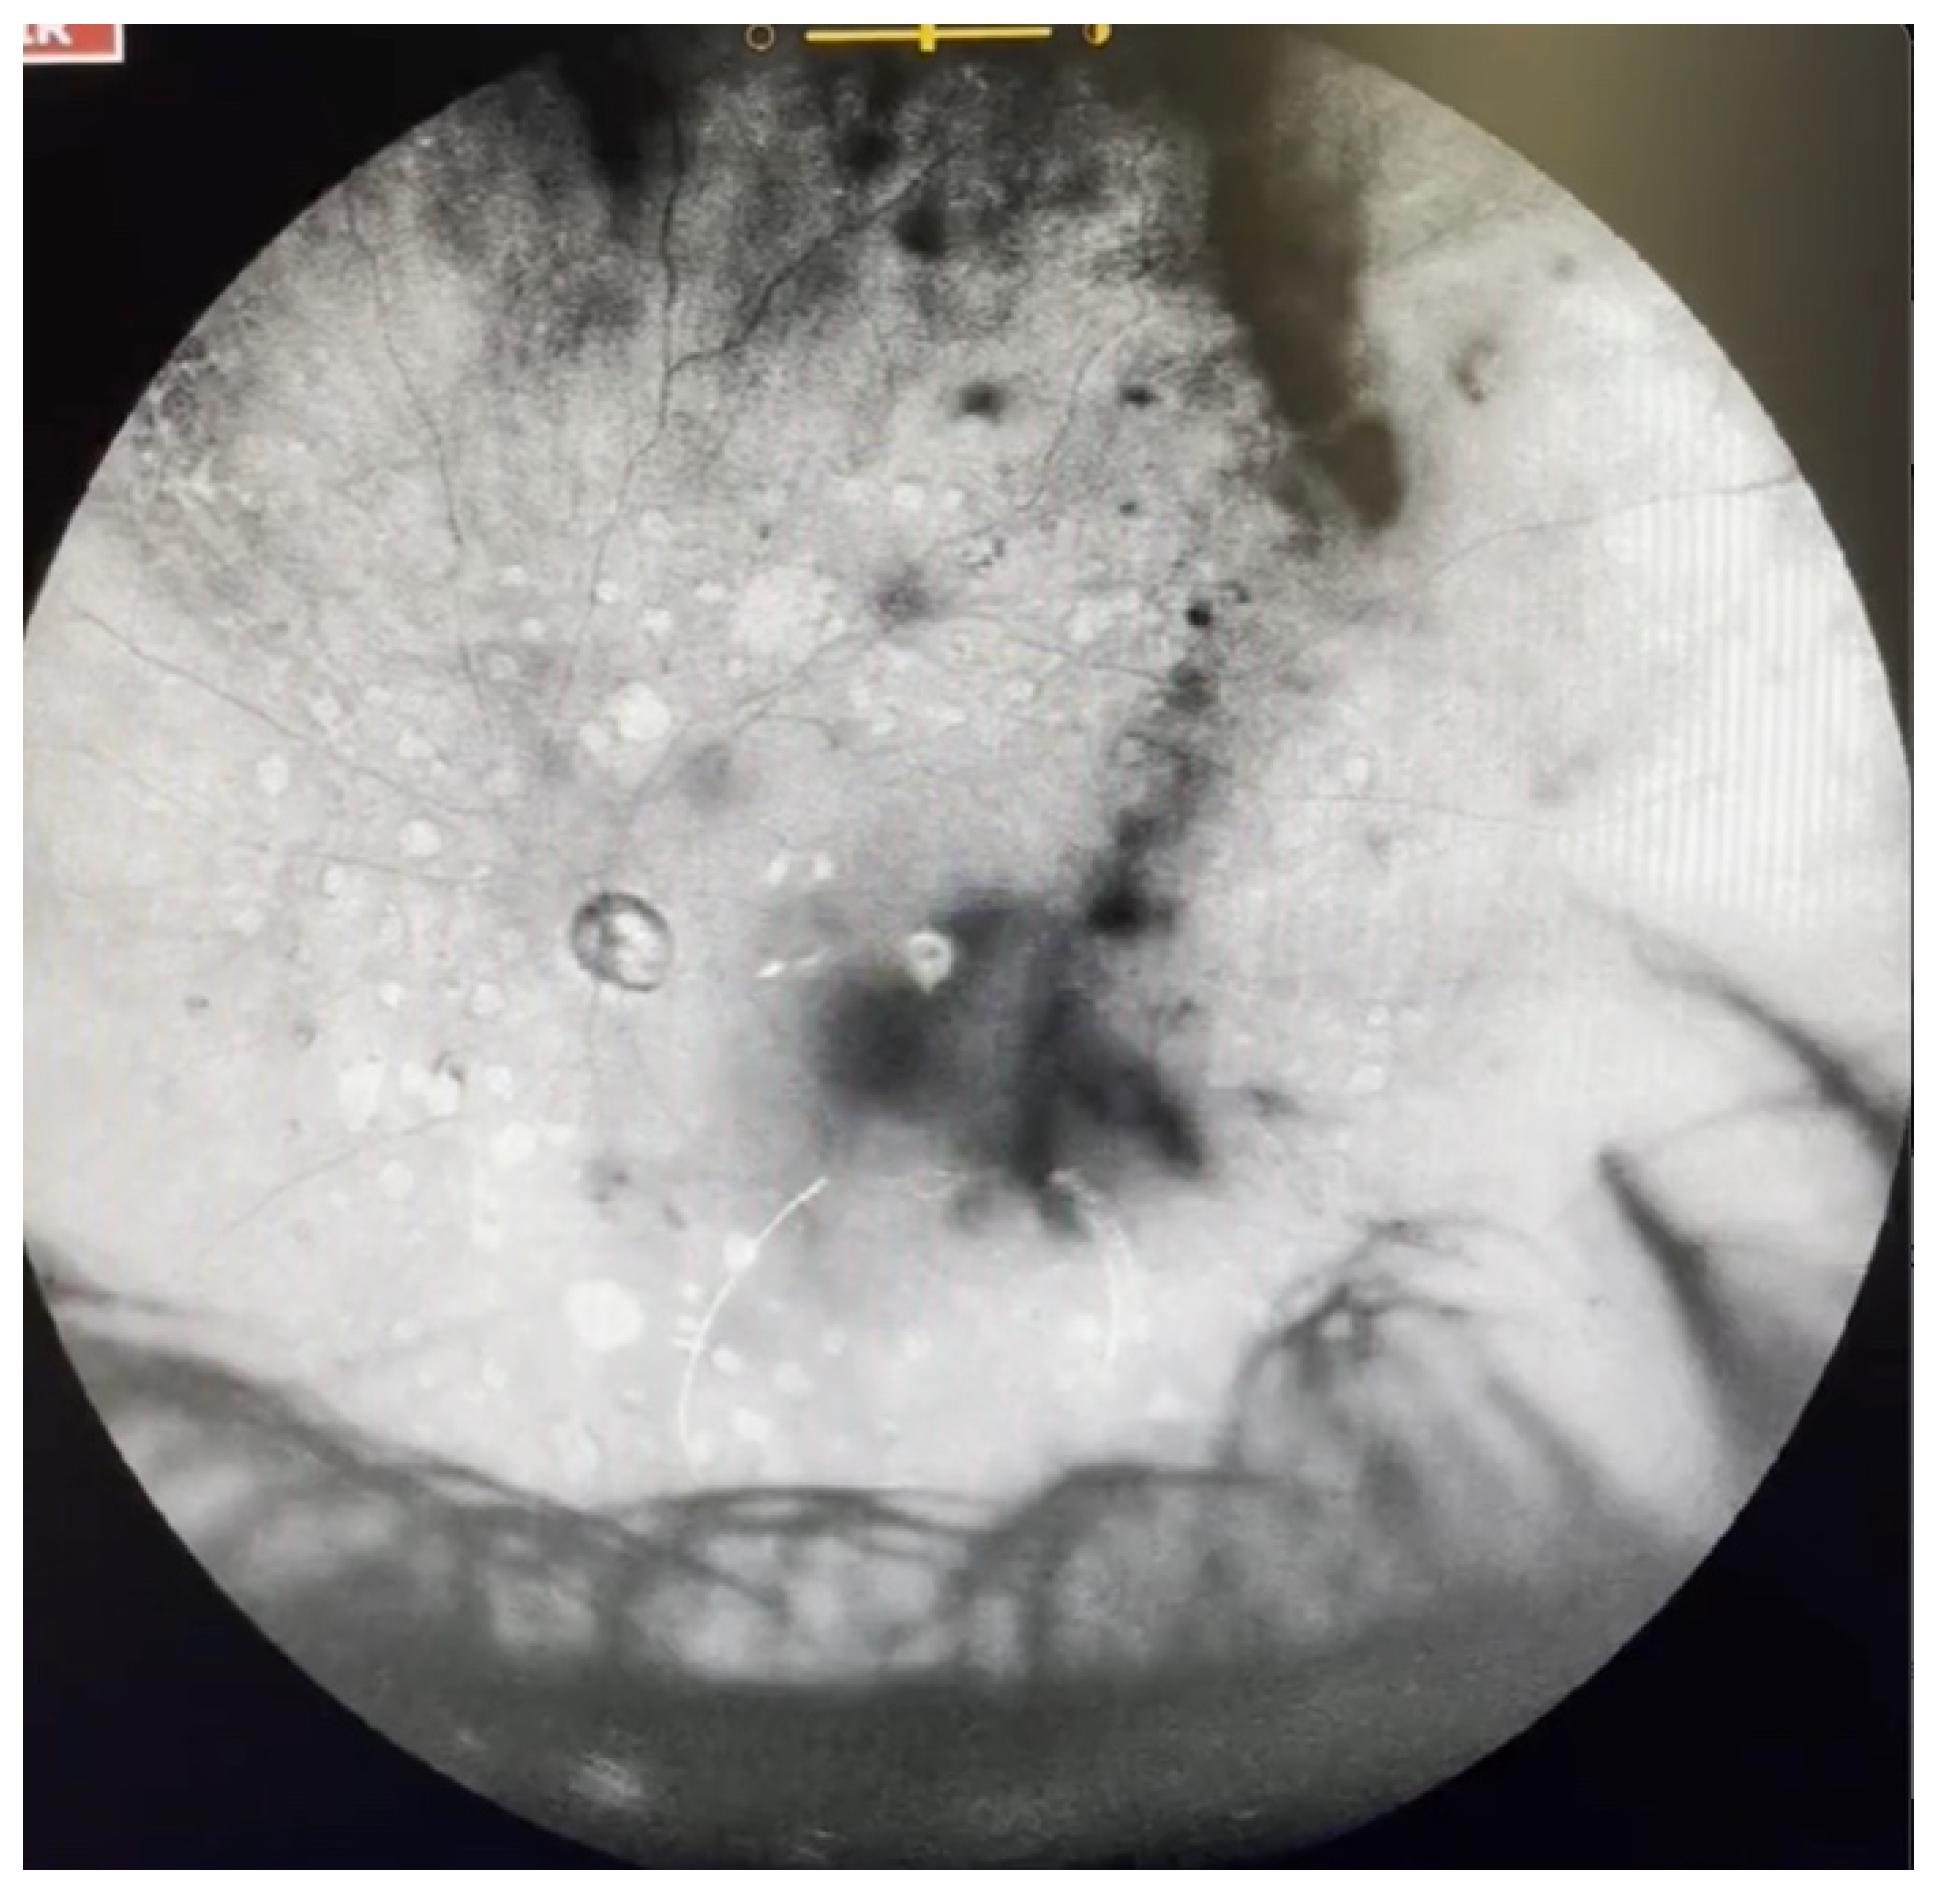

| Grade 5—Dense opacities that obstruct at least 30% of the macula (~2 disc diameters in size) (Figure 7 and Video S7). |